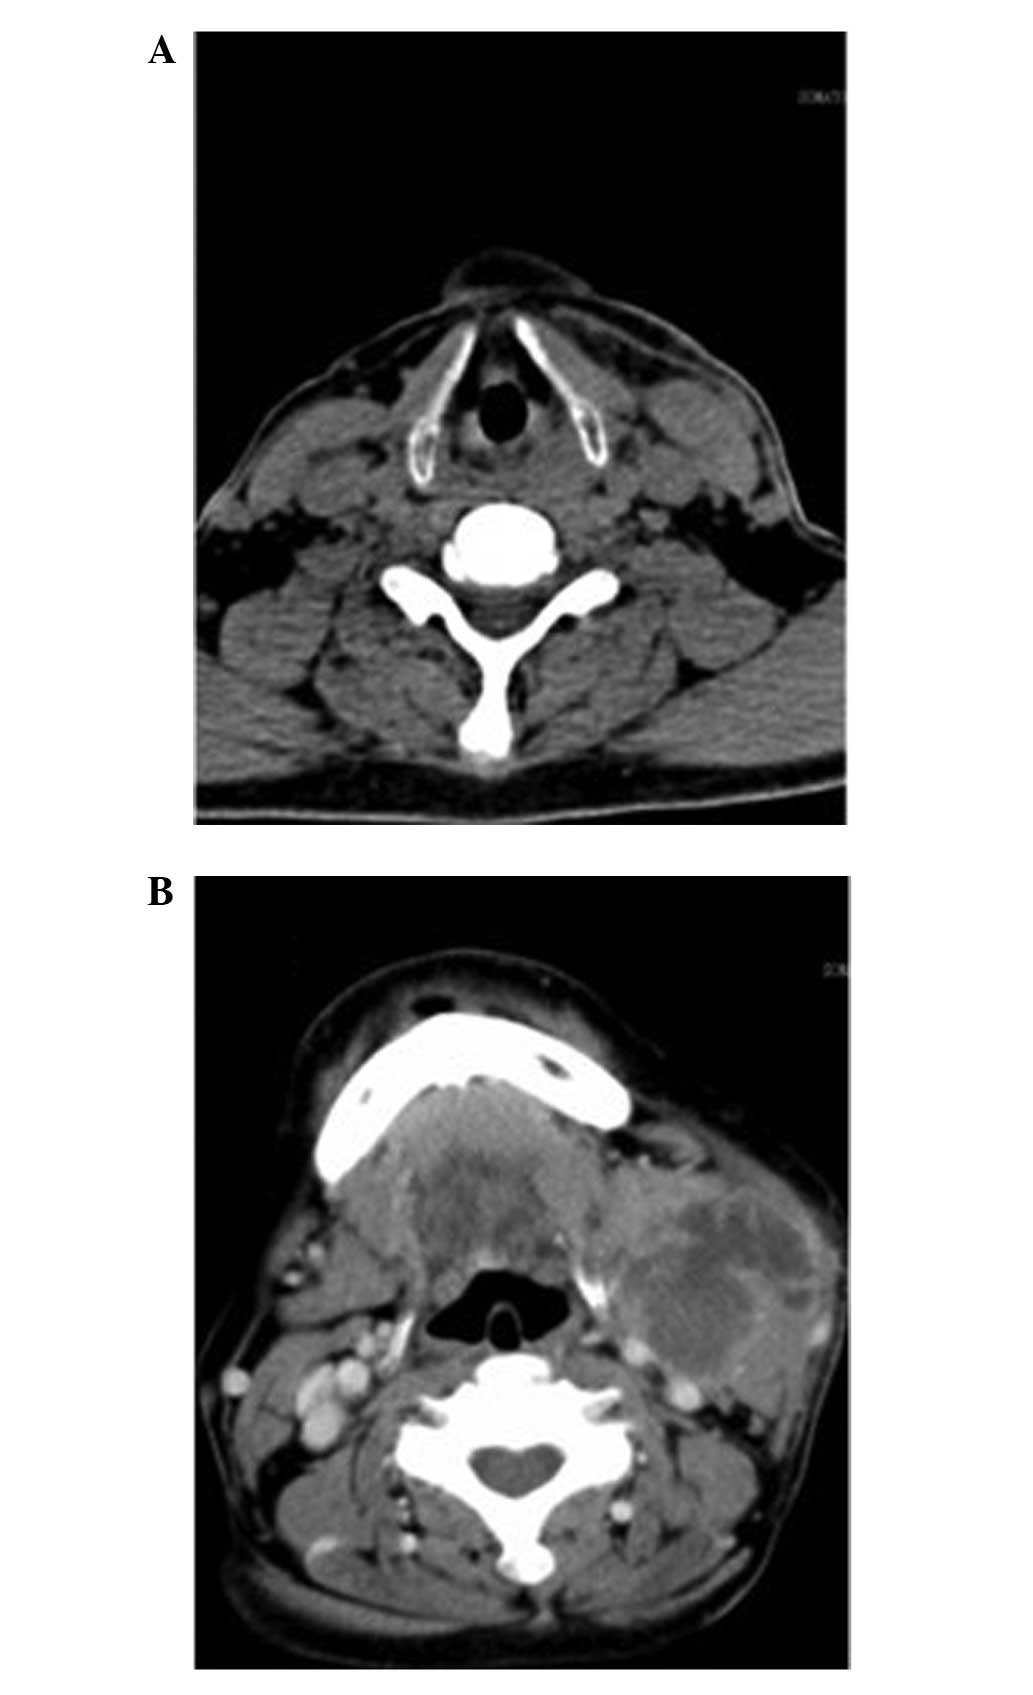

A 62-year-old male was admitted to the Department of Otolaryngology and Head and Neck Surgery, Sir Run Run Shaw Hospital (Hangzhou, China), to evaluate the presence of persistent hoarseness (six-month duration). An endoscopy demonstrated a mass on the left vocal cord, which markedly extended to the anterior commissure (Fig. 3). CT showed a 1.5×1.0-cm mass on the left vocal cord, at high resolution (Fig. 4). A total laryngectomy with neck dissection was performed. The surgically-removed tumor of the left vocal cord appeared cauliflower-like and was 1.5×1.3 cm in size. Follow-up of the patient 6 months postoperatively revealed pulmonary metastases.

A 57-year-old male presented at the Department of Otolaryngology and Head and Neck Surgery, Sir Run Run Shaw Hospital (Hangzhou, China) with a one-year history of pharyngeal foreign body sensation. An endoscopy and CT revealed a large mass on the posterior wall of the hypopharynx (Figs. 5 and 6). The patient was treated with a near total hypopharyngectomy followed by RFFF reconstruction. In addition, external radiotherapy was administered at the Taizhou Hospital (Taizhou, China). Metastases and recurrence were not clinically apparent at the 5.5-month follow-up. A summary of all three cases is presented in Table I.